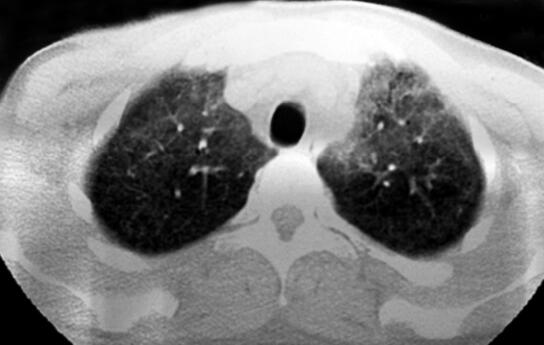

青年男性患者,农民,未婚,既往体健,否认呼吸系统疾病及其他慢性疾病史,无饲鸽、发霉物质接触史。1个月前受凉后出现发热,伴寒战,最高体温达40℃,呈稽留热,伴咳嗽、少许白痰,呼吸困难,活动后明显,无夜间憋醒,就诊于当地医院行胸部CT检查示:双肺对称的弥漫性分布的磨玻璃影(如图1、图2),予抗感染治疗,先后静脉滴注红霉素、头孢哌酮-舒巴坦半月余(具体用法用量不详),体温较前有所下降,但未降至正常,咳嗽、呼吸困难症状未见明显缓解,为求进一步诊治来诊。病来无胸痛、咯血,无腹痛、腹泻,无头痛,头晕,精神状态差,饮食睡眠差,二便可,近一月体重减轻约8kg。

图1

首次病史采集,按照常规问诊病史,但应注意以下细节详细询问协助明确诊断:患者既往体健,无呼吸系统疾病及其他慢性疾病史,此次发病主要症状为发热,伴有咳嗽、咳少许白痰、呼吸困难,按照常见病优先考虑原则应将呼吸道感染性疾病放在首位,但此次发病经过半个月的抗感染治疗,症状未见明显的缓解,那么原因有以下几种可能:①特殊的病原体感染,如结核、病毒及真菌等,普通抗生素治疗无效,可围绕以上特殊病原体感染的诱因、伴发症状进行询问;②先前使用的抗生素剂量不足,或者患者出现新的并发症如脓胸、脑炎等;③非感染性疾病,该患者病程中始终存在呼吸困难,气促、活动后加重,结合胸部CT示双肺对称的弥漫性分布的磨玻璃影,符合间质性肺疾病特点,考虑过敏性肺炎?淋巴细胞间质性肺炎?肺泡蛋白沉积症?在之后的查体、检查和治疗中,应该始终考虑以上几种原因,以更好的明确诊断。